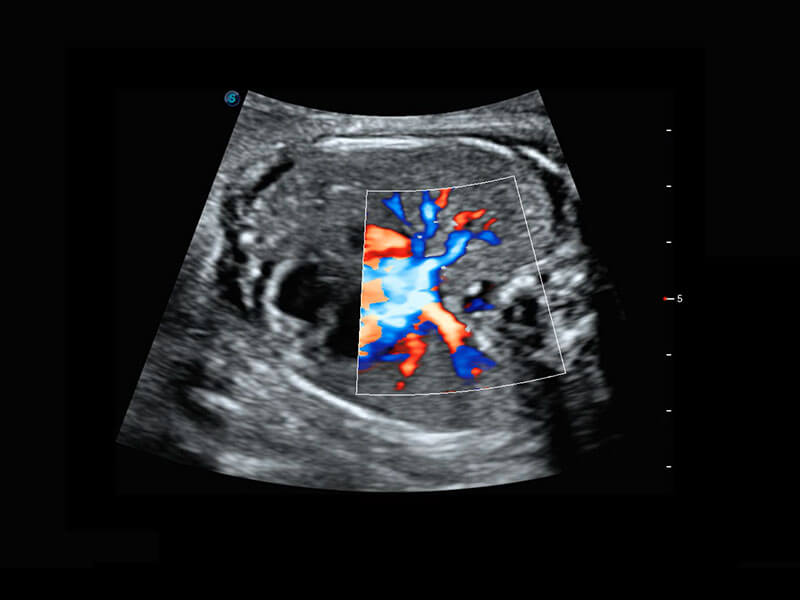

P60搭載一系列胎兒心臟成像技術(shù),實現(xiàn)精細的胎兒心臟評估。

四腔切面

四腔心血流

右室雙出口

胎心容積成像